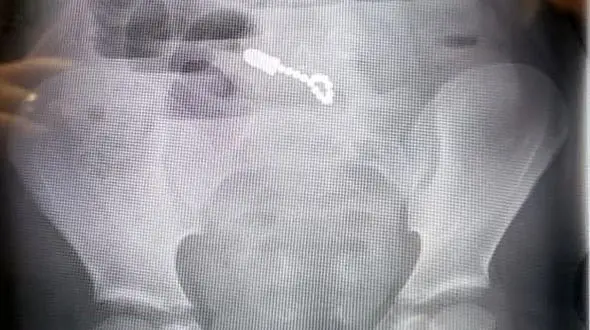

رکنا: پسربچهای که پنهانی با اسباببازیهای آهنربایی برادرش بازی میکرد وقتی متوجه حضور برادرش شد، اسباببازیها را بلعید و حالا پس از پشت سر گذاشتن سه عمل جراحی از خوردن و آشامیدن عاجز است.